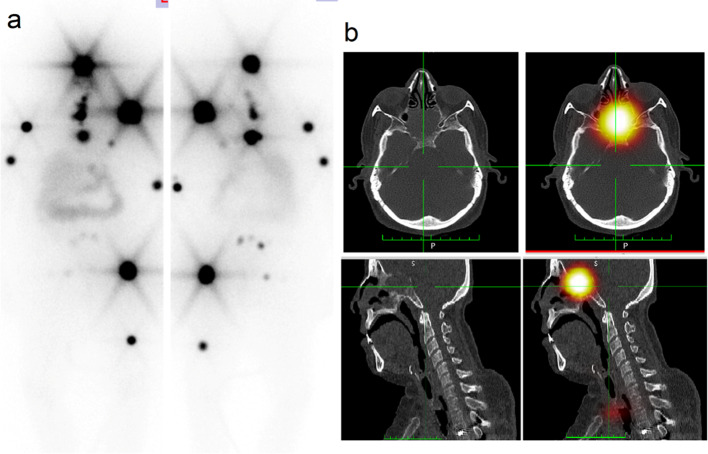

Regarding sites of metastatic disease, metastatic invasion of the skull bone is rare and develops in only 2.5%-5.8% of the cases and mostly affects the sella turcica, pituitary gland, cavernous sinus and sphenoid sinus (Osorio et al. 2017; Sheikh et al. 2018). Herrin we presented a case of sella turcica metastasis, she was treated by RAIT and RTH and still has evidence of residual disease like in our case Fig. 1. The reported incidence of renal metastases is about 3% for the papillary subtype and 6–20% for the follicular subtype (Falzarano et al. 2013; Patel et al. 2011). We reported 2 cases of renal metastases, one of them had papillary and the other had follicular carcinoma.

Fig. 1.

a WBI scan showed residual functioning thyroid tissue with multiple iodine avid skeletal metastases and b SPECT/CT images showed iodine avid destructive lytic metastatic lesions at sella turcica, 5th and 6th dorsal vertebrae and left humeral head, right humeral shaft and proximal end and mid shaft of left femur